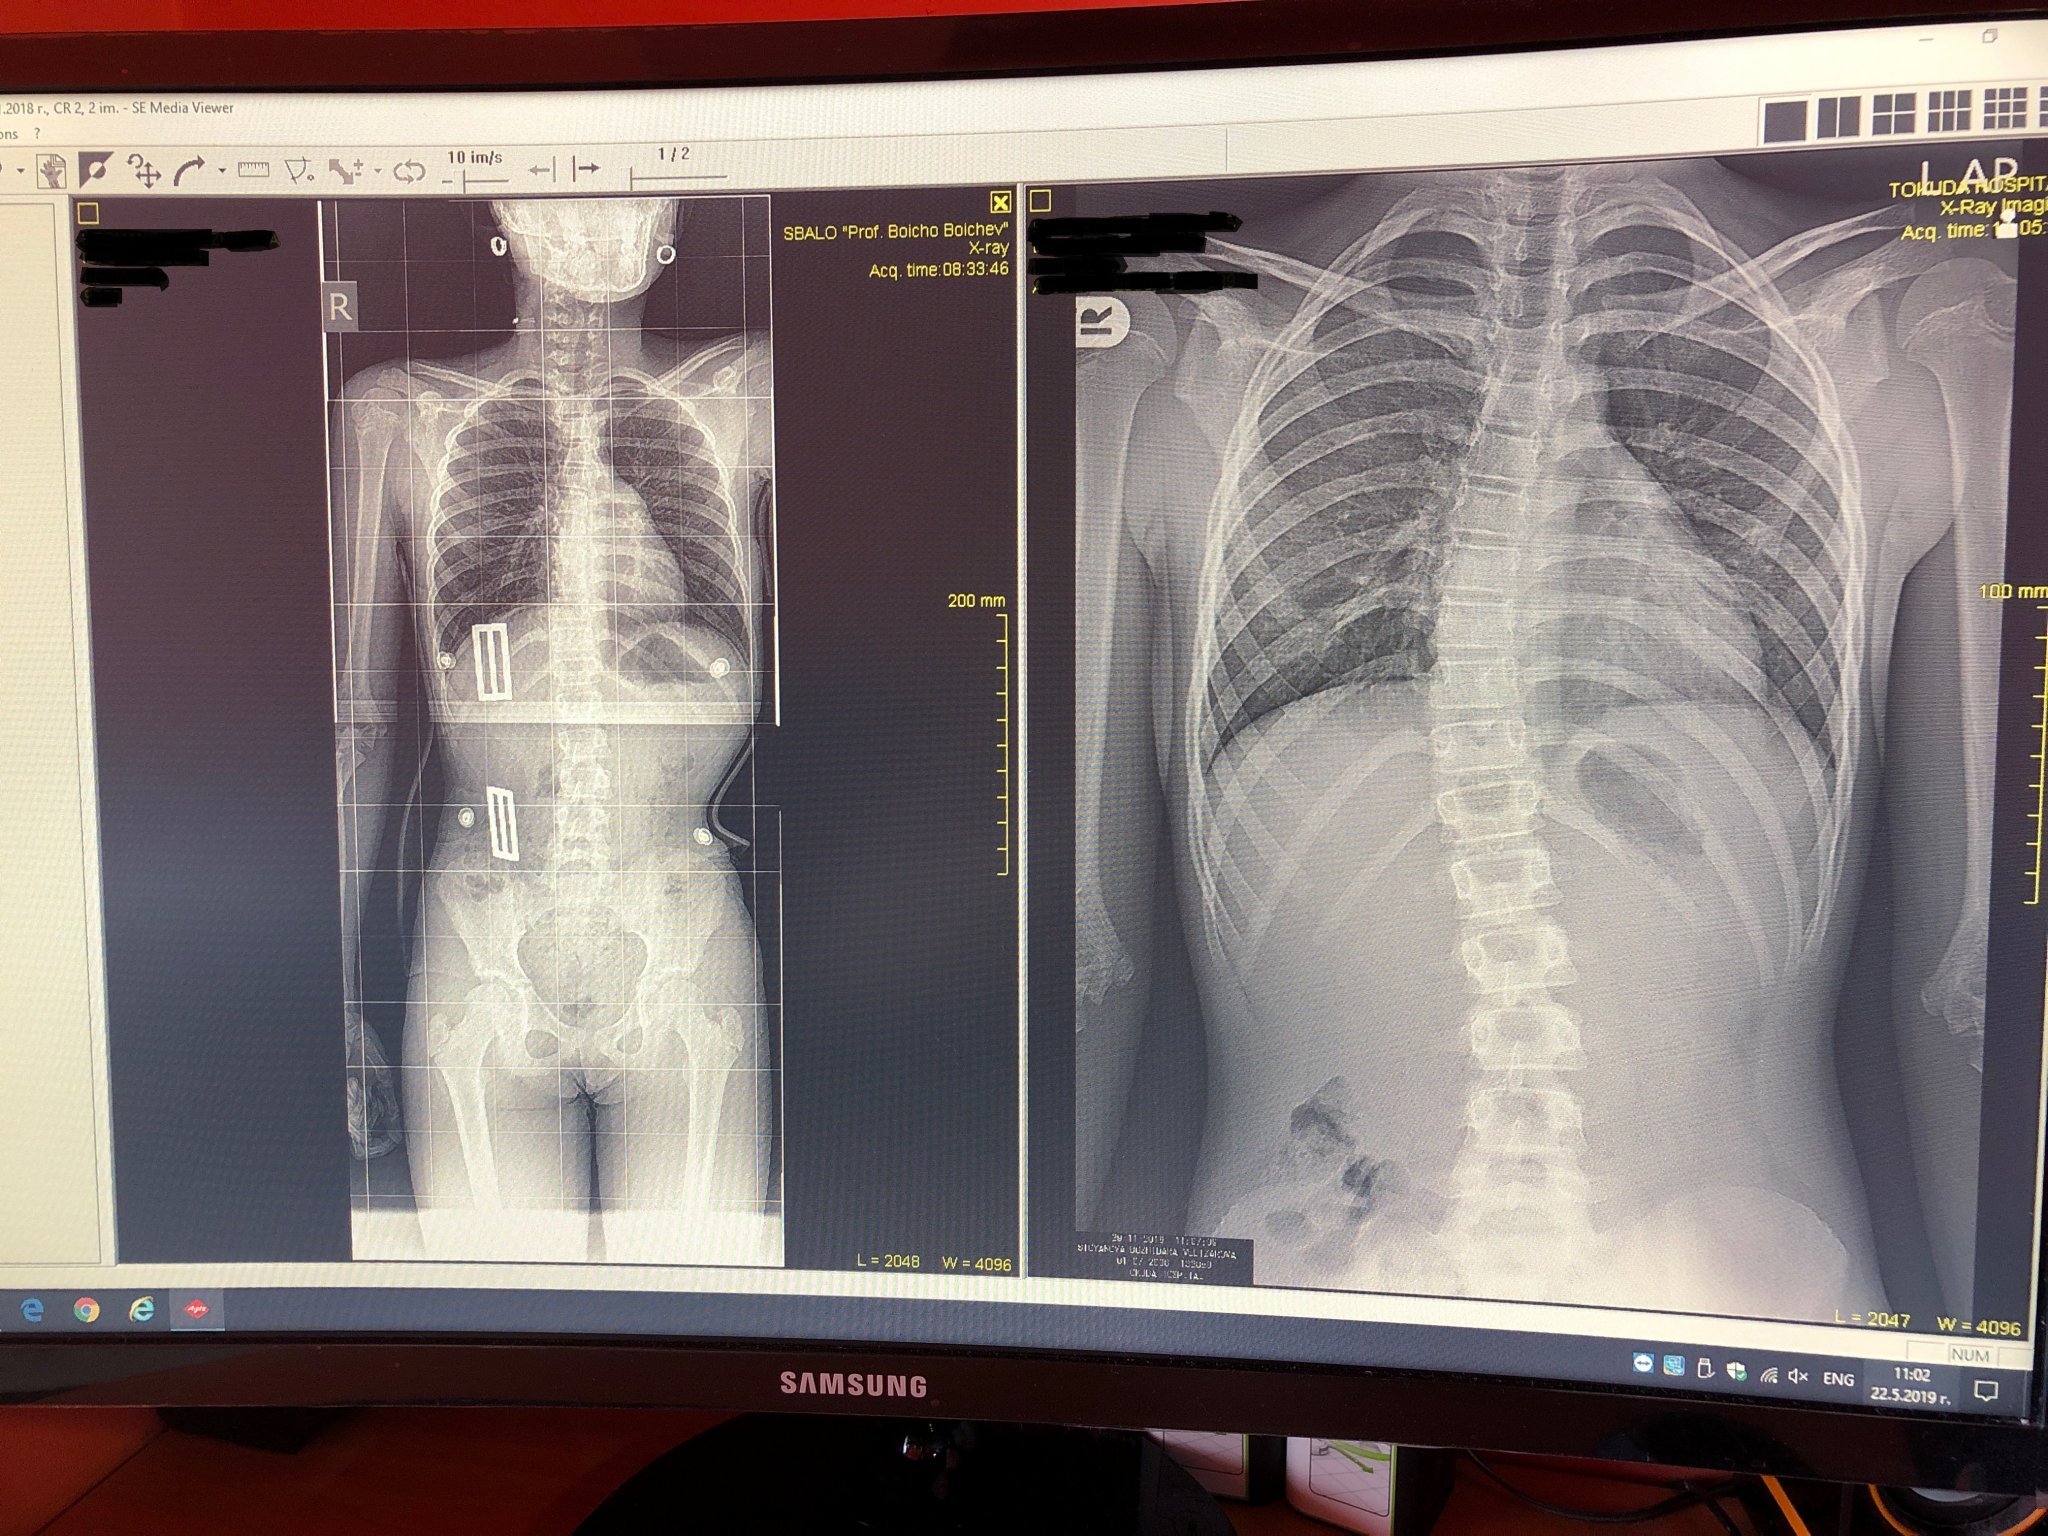

Какви са основните характеристики на сколиозата?

Каква е разликата между функционалната и структурната сколиоза?